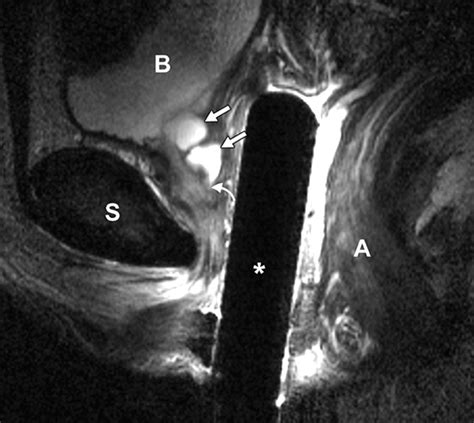

MRI (Magnetic Resonance Imaging) The gold standard for visualizing the size and location of the diverticulum.

The primary surgical goal is the complete excision of the diverticulum and the reconstruction of the urethral wall. Approaches include:

• Transvaginal Diverticulectomy: The most common approach, where the surgeon accesses the pouch through an incision in the vaginal wall.

• Layered Closure: After removing the sac, the urethral and vaginal tissues are closed in separate layers to prevent the formation of a fistula.